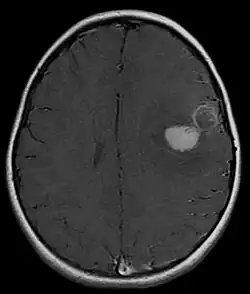

Primitive neuroectodermal tumor

Primitive neuroectodermal tumor is a malignant (cancerous) neural crest tumor.[1] It is a rare tumor, usually occurring in children and young adults under 25 years of age. The overall 5 year survival rate is about 53%.[2]

It gets its name because the majority of the cells in the tumor are derived from neuroectoderm, but have not developed and differentiated in the way a normal neuron would, and so the cells appear "primitive". PNET belongs to the Ewing family of tumors.